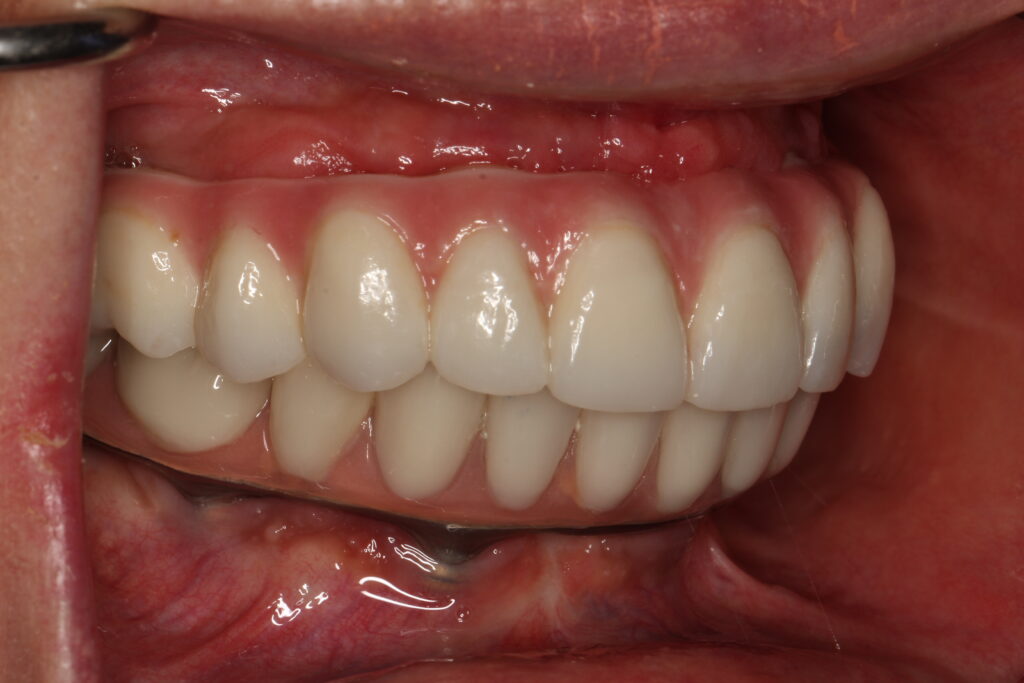

A selection of full arch fixed implant bridge patients after 5 years of wear